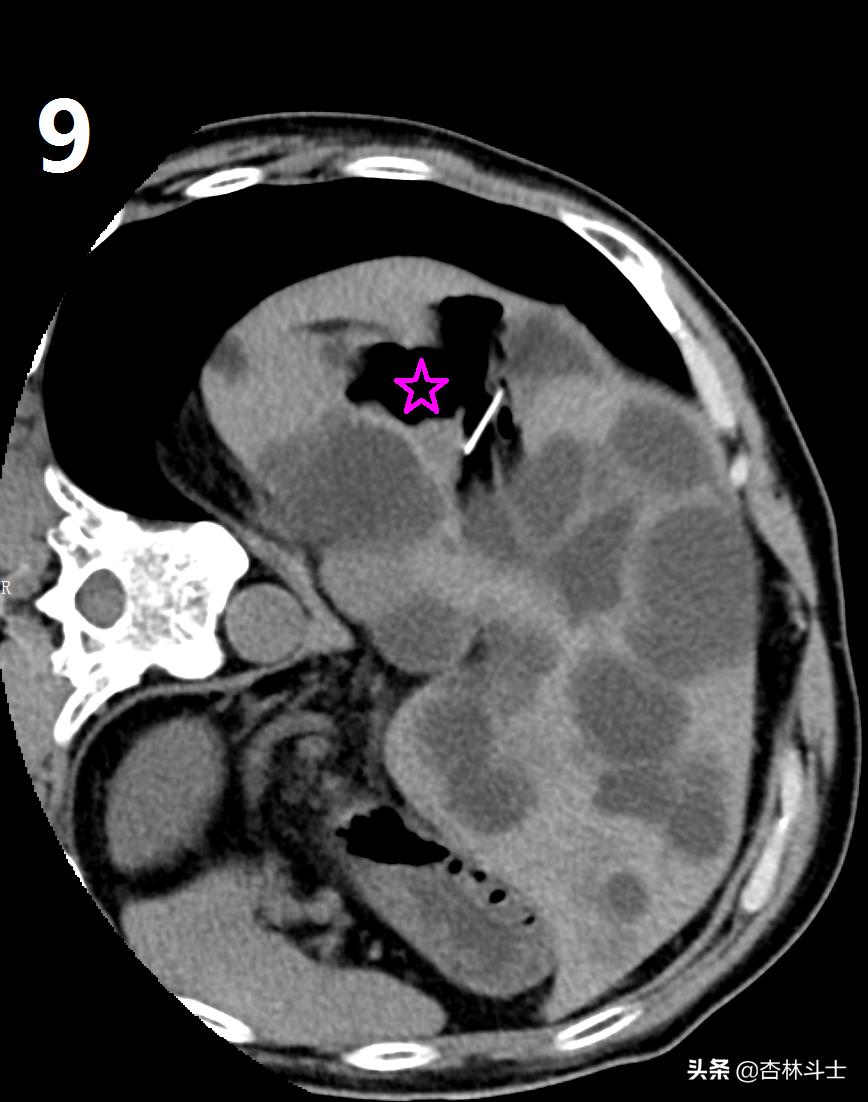

图7-8-9为上次做微创手术术中部分图像,红箭头所示为超细酒精抽吸硬化针,直径约0.79㎜,图9中五角星为囊腔内囊液被抽吸干净,最后一幅图是抽出来的黄色清澈囊液。同时被注入的无水酒精所代替。